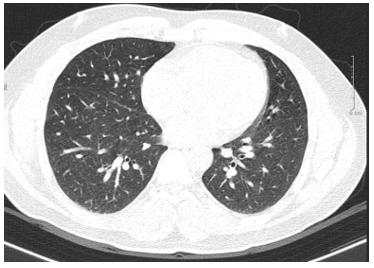

Chụp cắt lớp vi tính lồng ngực: Phổi phải nhu mô thùy trên sát rãnh liên thùy lớn có tổn thương dạng hang chứa khí kích thước 18x20mm, thành dày 8mm, bờ không đều. Nhu mô phổi còn lại có nhiều nốt đặc, nốt lớn nhất đường kính 13mm. Không thấy giãn phế quản - phế nang. Rãnh liên thùy phổi trái có nốt đặc bờ đều đường kính 2mm. Dịch khoang màng phổi phải dày 13mm.

Hình 1: Hình ảnh chụp cắt lớp vi tính lồng ngực: hình ảnh tràn dịch màng phổi phải và nhiều nốt đặc nhu mô phổi phải